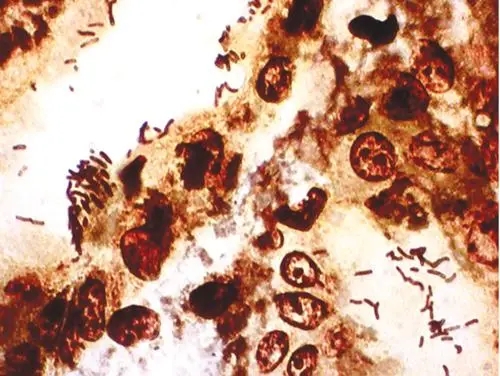

图片来源于百度